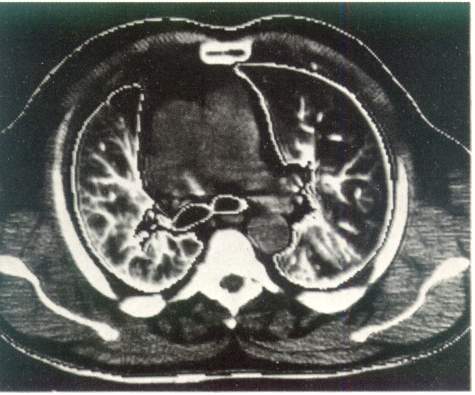

Возможности рентгенологической диагностики заметно расширились за счет становления и клинического использования компьютерной рентгенотомографии. По сравнению с обычной рентгенографией компьютерная рентгенография имеет в десятки раз большую разрешающую способность и позволяет различать ткани с разностью по плотности до 0,5 %. Это дает возможность четко определять границу между нормальной и патологически измененной легочной тканью. На компьютерных томограммах органов грудной полости удается не только локализовать патологический очаг, но и определить его размеры, оценить плотность и однородность, соотношение с соседними анатомическими образованиями и органами.

Рис. 3. Компьютерная томография органов грудной клетки. Норма.

Компьютерная томография дает возможность получить наиболее полную рентгенологическую информацию об опухолях и кистах средостения, сосудистых изменениях в легких, аневризмах, о состоянии трахеобронхиального дерева, характере и структуре «шаровидных образований в легких», патологических изменениях в плевре, грудной стенке, особенно при ее злокачественных поражениях (рис. 3).